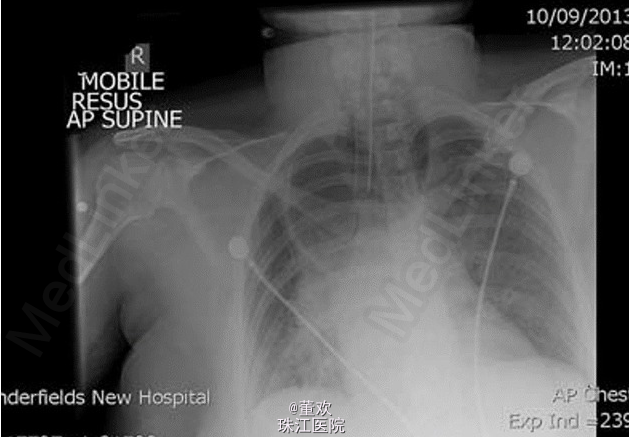

查体:双肺呼吸音较弱,右侧明显,无哮鸣音,未问及干湿性啰音。叩诊音未见明显异常。 辅助检查:胸片示右上肺透亮影;肺部 CT 示食管内有大量食物,呈显著扩张状态;严重压迫气管及气管内插管。具体图像如下。